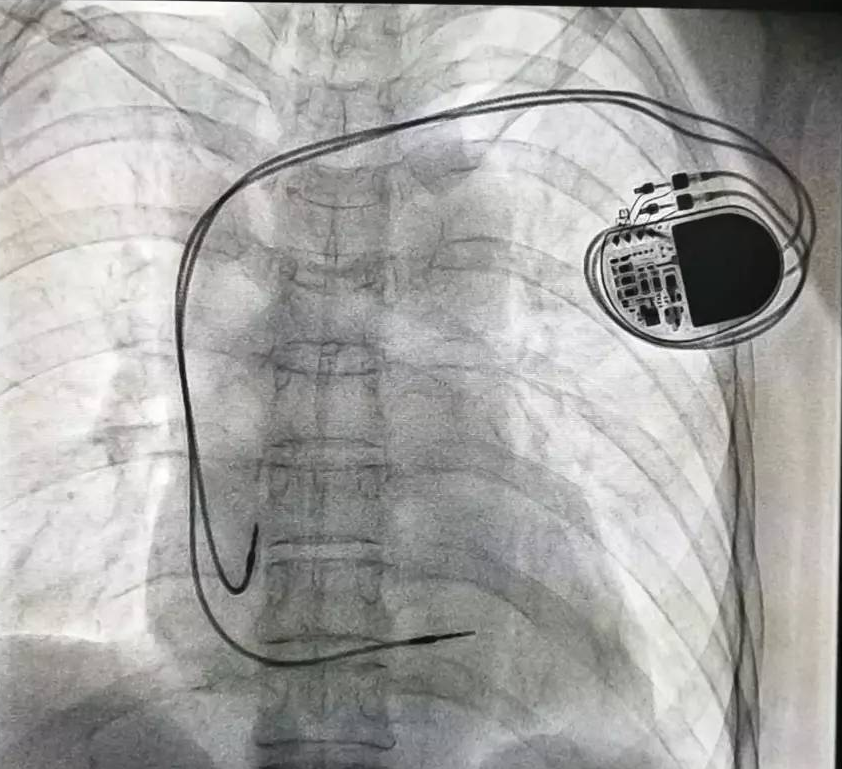

全球唯一!無(wú)線(xiàn)雙腔起搏器首次植入

來(lái)源:器械之家,未經(jīng)授權不得以任何形式轉載,且24小時(shí)后方可轉載。2022年2月7日雅培宣布,其在研型Aveir?雙腔無(wú)引線(xiàn)起搏器完成了全球首例患者植入,這也是全世界第一個(gè)雙腔無(wú)線(xiàn)起搏器。Aveir?DR雙腔起搏器提供右心房和心臟右心室的同步、逐次跳起搏,近80%接受起搏器治療的患者需要雙腔選擇,A